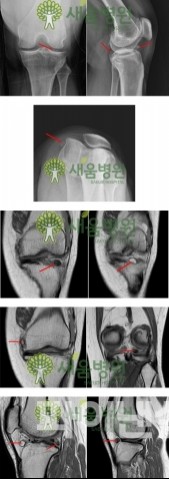

보다 심층적인 분석이 필요한 경우, MRI, X-ray, 초음파 검사 등 다양한 영상 진단법이 시행됩니다. 이러한 검사는 병변의 거의 모든 세부 사항을 파악할 수 있게 해줍니다. 특히 MRI는 연조직을 잘 보여주기 때문에 관절의 상태를 확인하는 데 유용한 도구로 간주됩니다.

- MRI(자기공명영상): 연골, 힘줄, 인대 등을 자세하게 볼 수 있습니다.

- X-ray: 뼈의 구조적 문제를 진단하는 데 효과적입니다.

- 초음파 검사: 수분의 유무, 염증 상태를 확인할 수 있습니다.